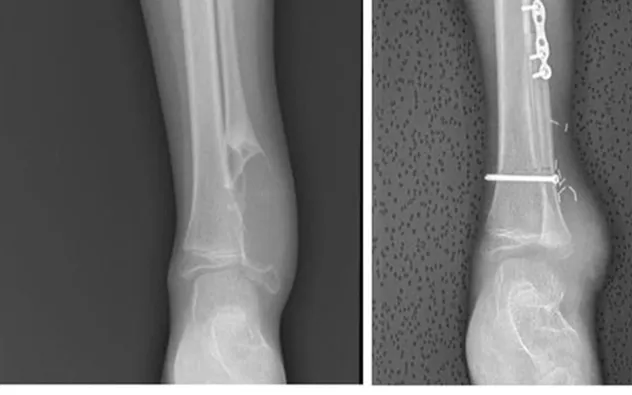

Theo thông tin từ bệnh viện, bé gái được phát hiện bất thường từ nhỏ nhưng quá trình tái khám bị gián đoạn. Khi nhập viện trở lại, khối u đã phát triển lớn, xâm lấn toàn bộ mắt cá ngoài và chèn ép nhiều cấu trúc quan trọng. May mắn, kết quả đánh giá cho thấy bệnh chưa di căn, tạo điều kiện để can thiệp triệt để.

Các bác sĩ đã tiến hành cắt bỏ toàn bộ khối u theo đúng nguyên tắc phẫu thuật ung thư, bảo đảm diện cắt an toàn. Thách thức lớn nhất là tái tạo cấu trúc cổ chân sao cho vừa giữ vững trục chi, vừa bảo tồn chức năng vận động lâu dài cho trẻ.

Ê-kíp quyết định áp dụng kỹ thuật ghép chỏm xương mác có cuống mạch, kết hợp vi phẫu nối mạch và tái tạo hệ thống dây chằng cổ chân. Ca mổ kéo dài 8 giờ, đòi hỏi sự phối hợp chặt chẽ của nhiều chuyên khoa và độ chính xác cao trong từng thao tác nhằm tránh tổn thương mạch máu, thần kinh.